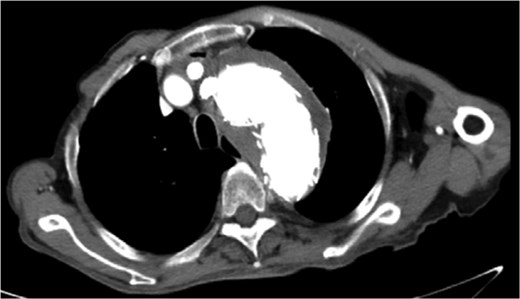

Despite recovery, the patient remained physically exhausted and required ongoing rehabilitation. In May 2023, after a COVID-19 infection, the patient experienced blood in phlegm. CTA confirmed successful aneurysm repair with no endoleak (Fig. 3). Thus the patient was hospitalized in the respiratory department. Relevant pulmonary examination indicators and lung CT results revealed no lung lesions associated with blood in sputum (Fig. 4). However, throughout July, 2023, intermittent blood in phlegm continued, and a CTA on July 19, 2023, revealed a type IV endoleak (Fig. 5). Conversely, aortography on July 27, 2023, showed no obvious endoleak. Closed drainage of the left thoracic cavity was performed, but blood in phlegm recurred on August 9, 2023. A Gore C-TAG stent graft was deployed in the thoracic aortic arch, with its proximal end anchored at the ostium of the left subclavian artery stent graft to ensure complete coverage of the endoleak site both proximally and distally(Fig. 6). Post-surgery, blood in phlegm symptoms abated.

Lung CT results revealed no lung lesions associated with blood in sputum.

In July 2023, endoleak was observed upon reexamination, possibly of stent graft origin.